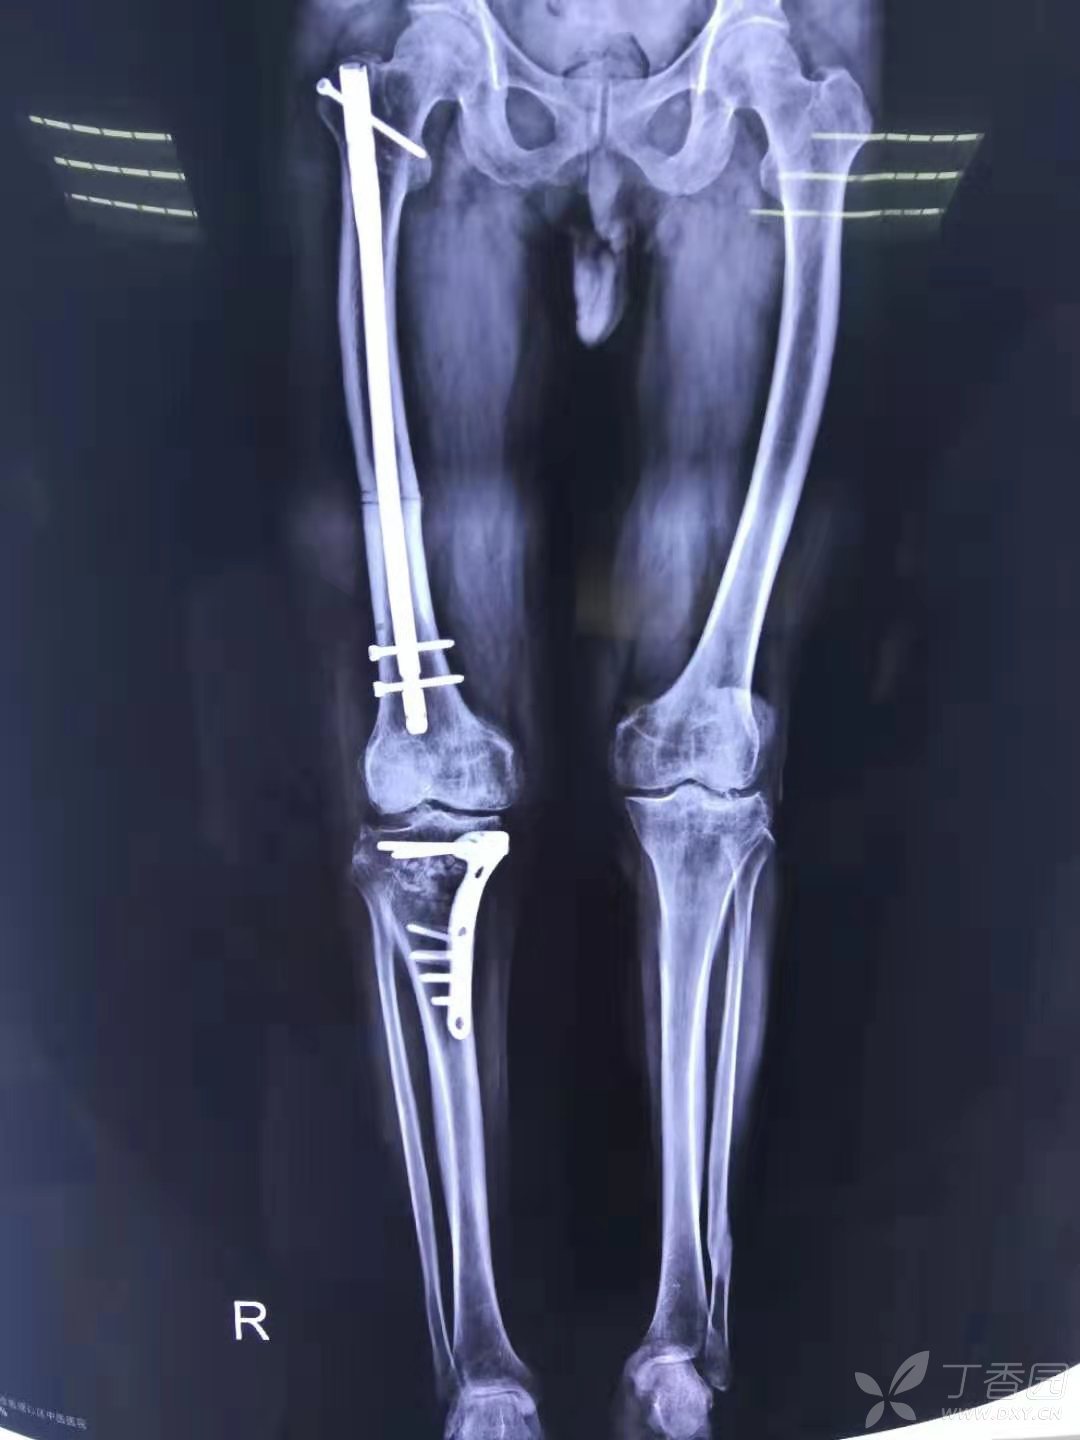

保膝术: 股骨远端截骨在膝外翻治疗中应用! - 好大夫在线

图片尺寸2448x3264